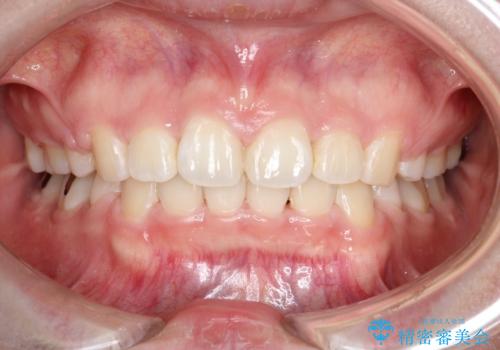

- 口元が出ていることを主訴に来院されました。

上下左右小臼歯を抜歯して審美装置で治療を行いました。

口元もスッキリと変化し、大変満足していただきました。